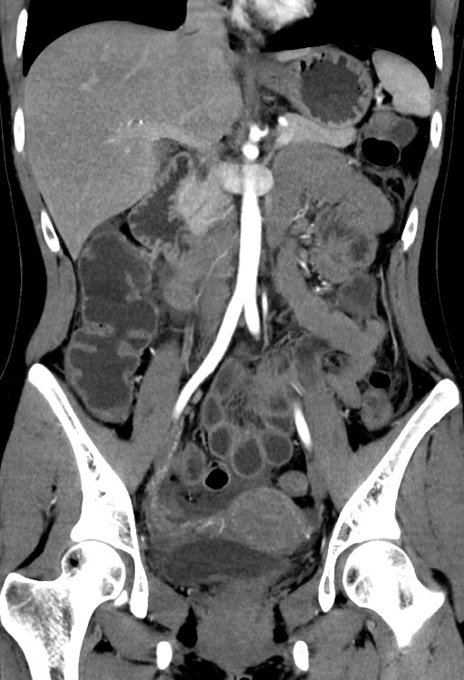

症例17(冠状断像)

【症例】20歳代女性

【主訴】嘔吐、下腹部痛

【現病歴】昨日夕食後に嘔吐し下腹部痛が出現。本日になっても嘔吐持続し改善しないため来院。

【身体所見】意識清明、BT 37.2℃、BP 108/67mmHg、腹部:平坦、やや硬、下腹部正中から右にかけて圧痛あり、反跳痛軽度あり、tapping pain(+)。

【データ】WBC 13600、CRP 14.94